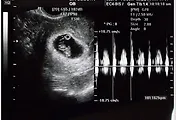

장안동의 린산부인과를 다녀왔다.

주위사람들이 임신테스트 후 바로 산부인과에 가면 임신 일수가 얼마 되지 않아 애기집이 안보인다고 좀 늦게 가는것을 권했다. 그 얘길 듣고 1주일 정도 늦쳐서 갔는데 벌써 7주가 지났다고 한다. 많이 자랐다고^^. 의사선생님도 조금 늦게온게 잘한거라고 말씀하시고... 일찍가면 병원을 한두번 더 가야한다는.

심장뛰는 소리도 듣고 머리며 팔이며 얘기를 해주는데 어찌나 신기하고 감동스럽던지.

예정일은 5월 초순. 2주 후에 좀더 정확히 알려준다고 한다.